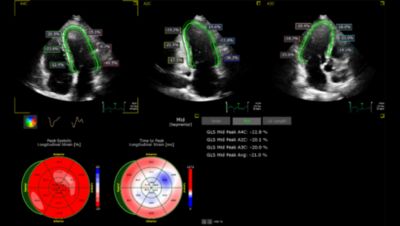

AI apps run in the background during image capture to identify images based on a selected application such as Strain.

Fully automated 2D doppler, length and strain measurements.

AI-driven automated measurements, from AI features such as Auto Measure and AutoStrain, reduce the number of keystrokes and clicks6, potentially alleviating the physical burden on clinical sonographers.